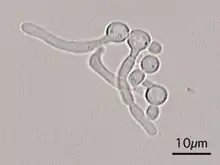

This "hyphal" denomination is due to Hwp1 appears exclusively on the surface of a projection called hyphae that emerges from the surface of this fungus.

Candida Albicans Yeast forms (round-to-oval)

Candida Albicans Hyphal forms (filamentous projections called hyphaes emerging from round-to-oval forms)